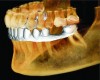

Figure 2 Integration of an optical scan of the mandible into the volume rendering of a CBCT scan.

Figure 2